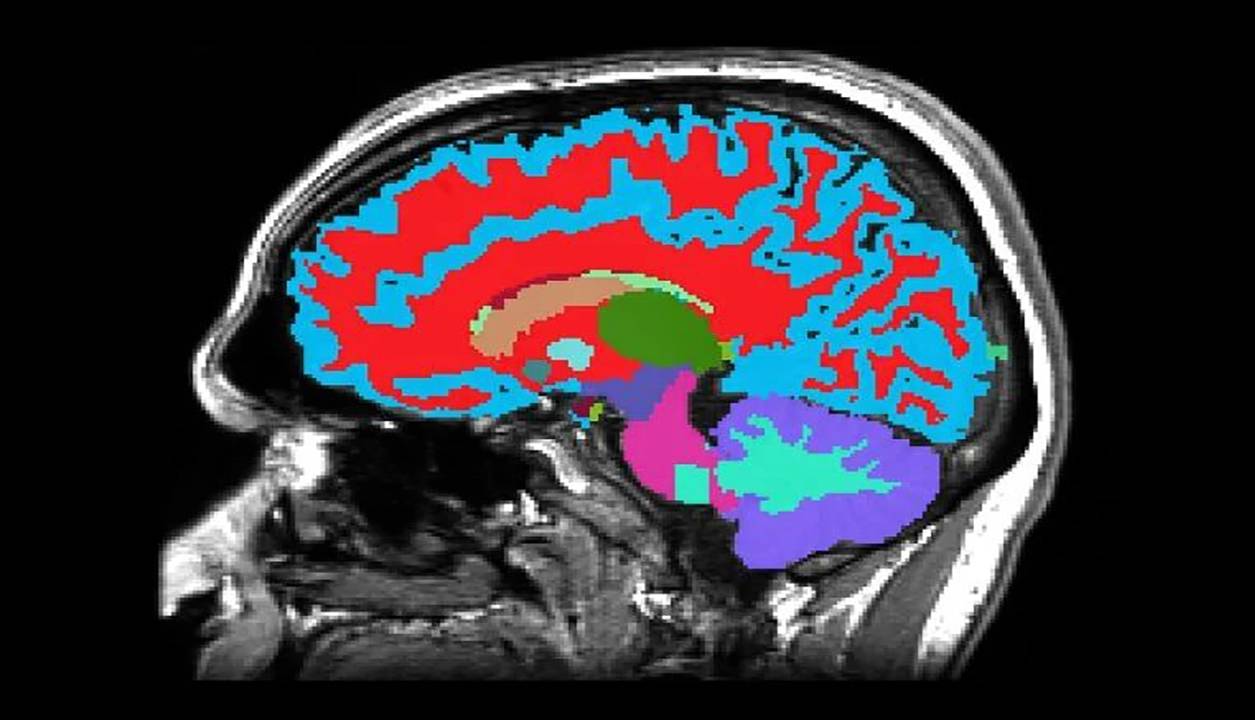

دانشمندانی از دانشگاه دوک و دانشگاه هاروارد در آمریکا و دانشگاه اوتاگو در نیوزیلند، ابزار جدید قدرتمندی ساختهاند که سرعت واقعی پیر شدن افراد را نشان میدهد و تنها چیزی که برای آن لازم است، یک تصویر لحظهای از مغز است.

این ابزار میتواند با یک اسکن اِمآرآی، خطر ابتلای افراد به بیماریهای مزمن را در مراحل بعدی زندگی آنها، مدتها قبل از بروز هر گونه علائم، تخمین بزند. این بینش اولیه میتواند به افراد کمک کند که در سبک زندگی و رژیم غذایی خود تغییراتی ایجاد کنند تا برای مدتی طولانیتر سالم بمانند.

این اسکن حتی میتواند احتمال ابتلای افراد مسن به زوال عقل و سایر بیماریهای مرتبط با افزایش سن را پیشبینی کند؛ هر قدر این خطرات زودتر شناسایی شوند، احتمال کاهش سرعت پیشرفت آنها بیشتر میشود و بهتر میتوان آنها را مدیریت کرد.